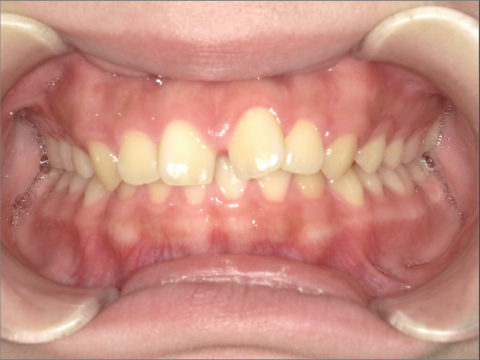

ご年齢 15歳女性

治療期間 2022/07/02〜2023/12/02(1年5ヶ月)

診断 110,000円(税込)

アライナー 660,000円(税込)

リテーナー 55,000円(税込)

BEFORE

AFTER